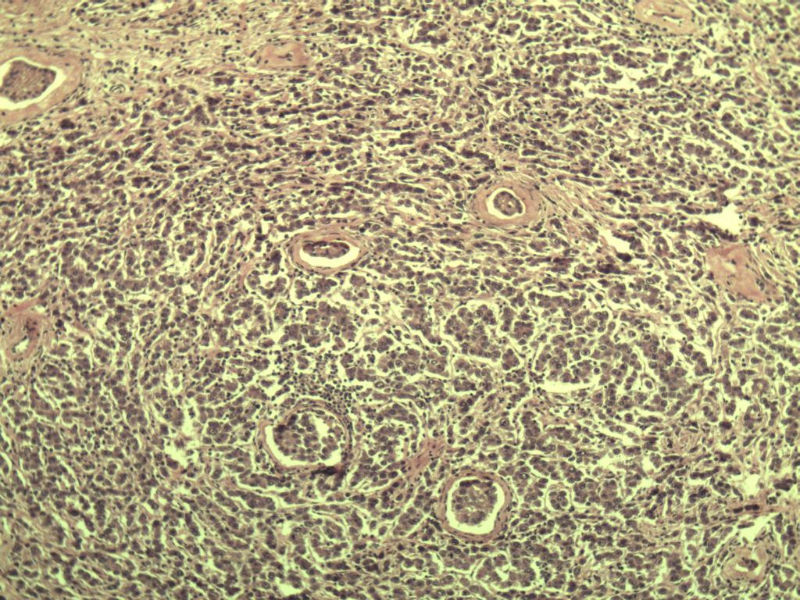

男 27岁 腹腔隐睾 5*3*2 cm, 切面灰红灰黄、实性、质中,请各位老师看看,是精原细胞瘤吗?感觉不像.